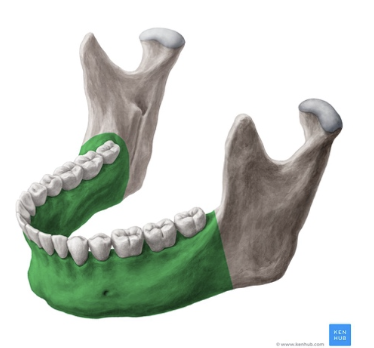

Mandíbula

Cuerpo Mandibular

Ramas mandibulares

Porción alveolar